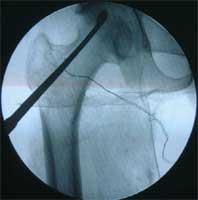

股骨头缺血性坏死MRI显示坏死区          微创手术方法,采用隧道减压刮除死骨

BMP植入,异体骨支撑,恢复形态     手术后24个月X线片,关节塌陷未加重,关节功能良好,无疼痛